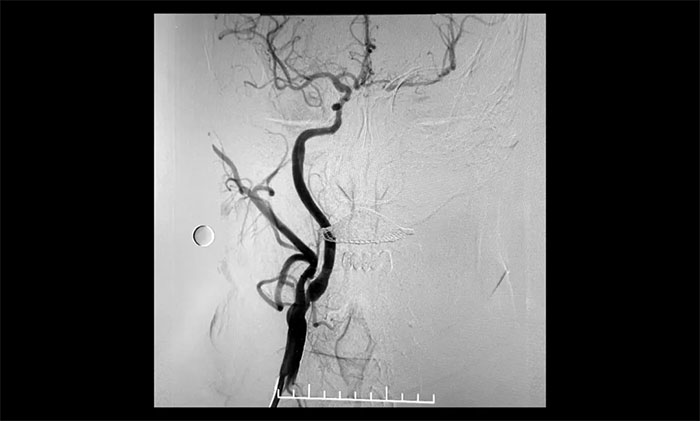

經(jīng)微導絲成功進入狹窄、閉塞頸內(nèi)動脈,在支架保護下,進行球囊逐段擴張,支架置入……,經(jīng)多次球囊擴張,置入支架后,造影顯示左頸內(nèi)動脈起始段狹窄明顯改善,左頸內(nèi)動脈顱內(nèi)段順利再通,左頸內(nèi)動脈眼動脈段、后交通段狹窄明顯改善。造影及3D造影見左頸總動脈、左頸內(nèi)動脈、左大腦中動脈顯影可,行支架CT見顱內(nèi)支架成形可,手術取得成功!

術后,患者生命體征平穩(wěn),無新發(fā)神經(jīng)功能障礙。術后,患者言語不利、肢體活動不利等癥狀明顯好轉。

▲ 術后,右頸內(nèi)動脈起始段狹窄明顯改善

▲術后,左頸內(nèi)動脈起始段狹窄明顯改善,左頸內(nèi)動脈顱內(nèi)段順利再通,左頸內(nèi)動脈眼動脈段、后交通段狹窄明顯改善